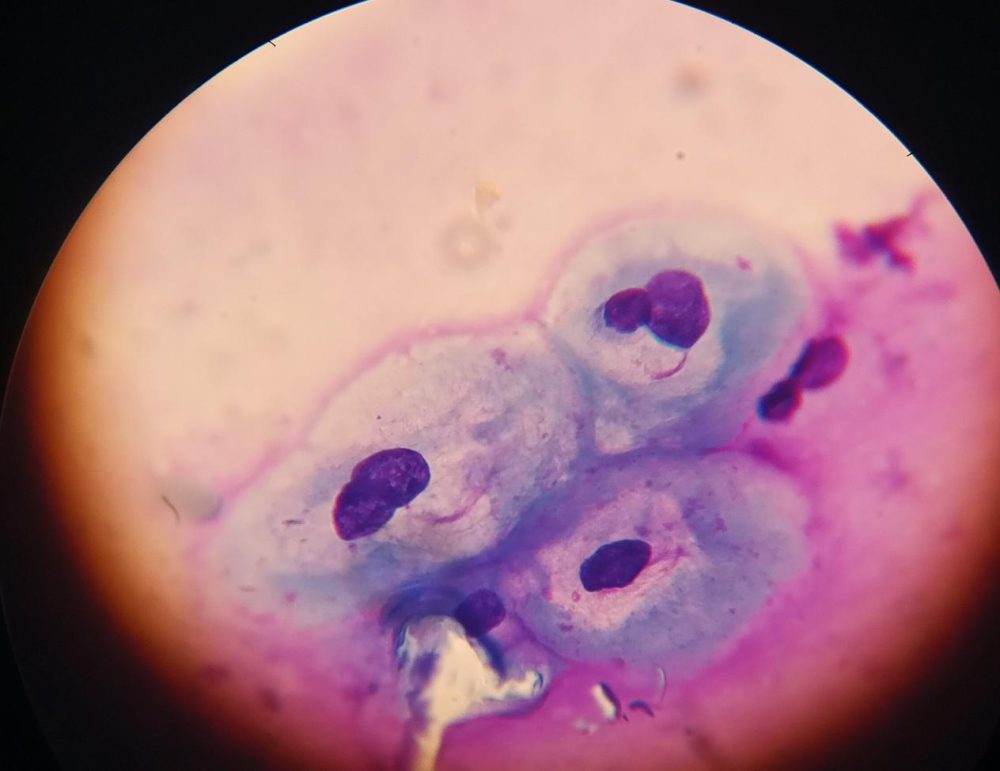

А вот главный «пакостник» – вирус папилломы человека. И те самые клетки плоского эпителия, пораженные им.

Если ВПЧ в клетках существует длительно, развивается дисплазия, то есть, предраковое состояние – вот как это выглядит.